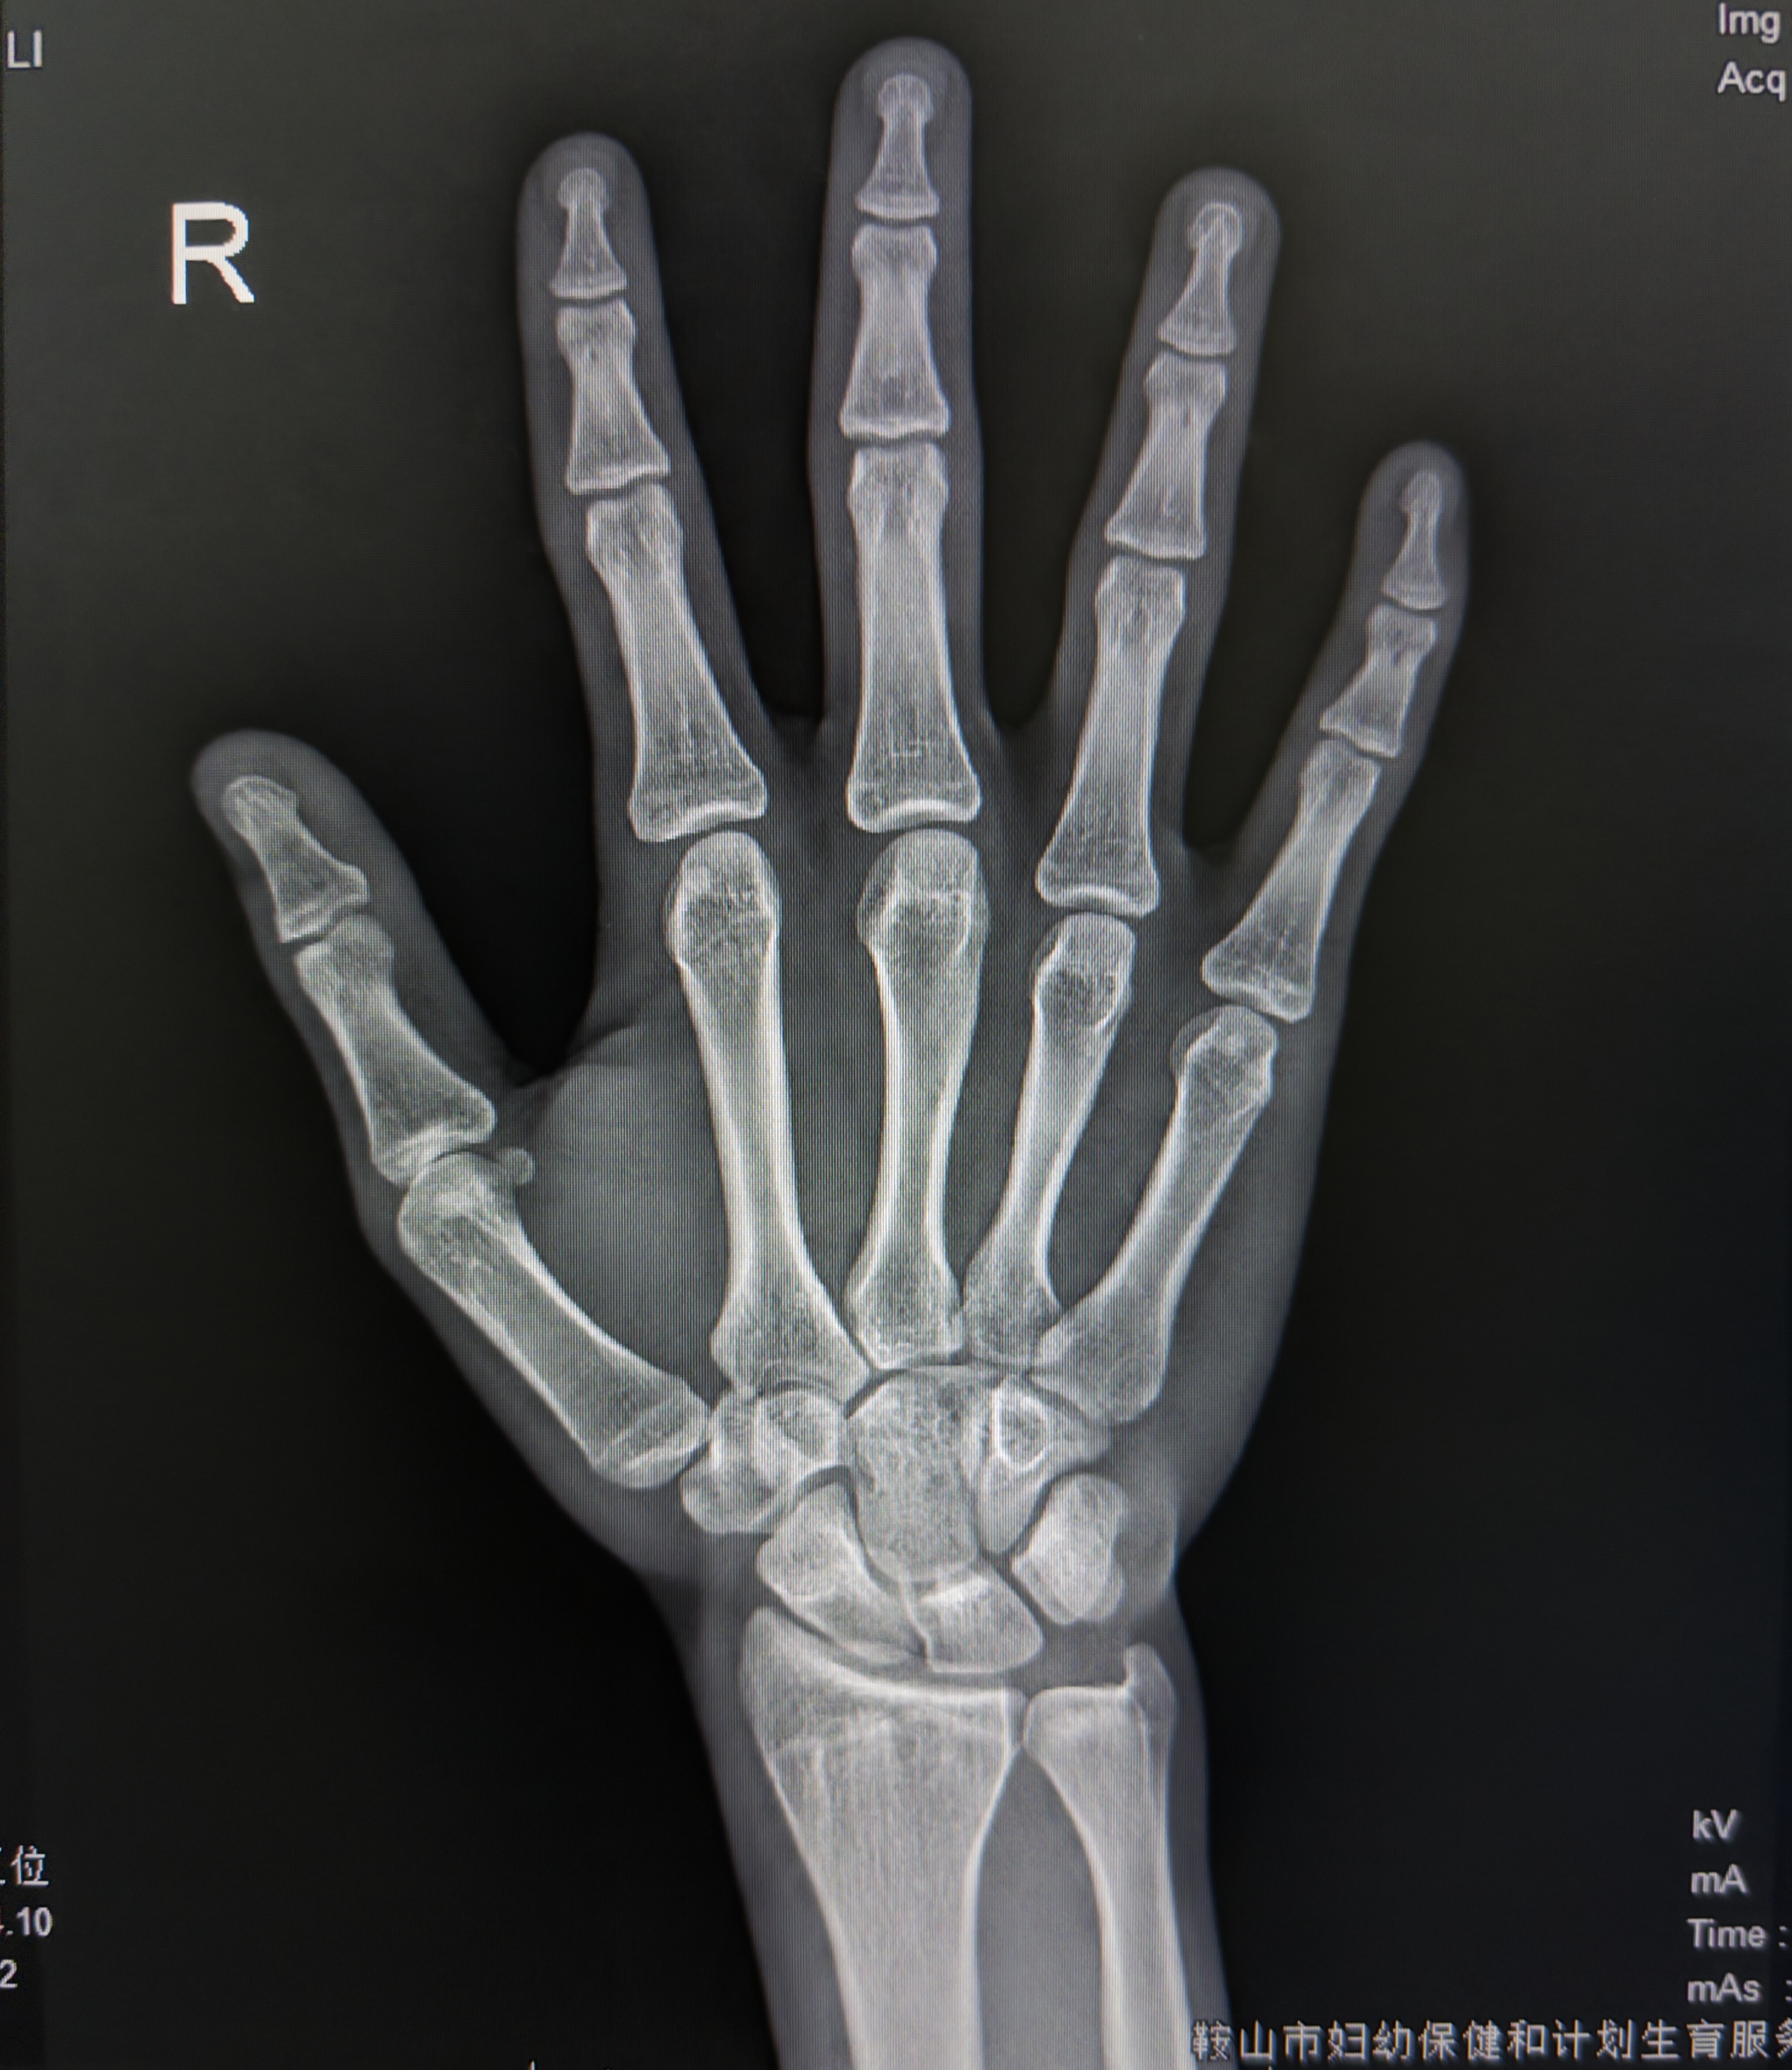

Doctor says growth plates are basically fused

Went for a health check up towards the end of my Easter holiday and got hit with gut wrenching news. At only 17.9, my growth plates have basically fully fused and my doctor says that HGH isn’t worth the risk of acromegaly.

plates are completely fused

At only 17.9, my growth plates have basically fully fused and my doctor says that HGH isn’t worth the risk of acromegaly.